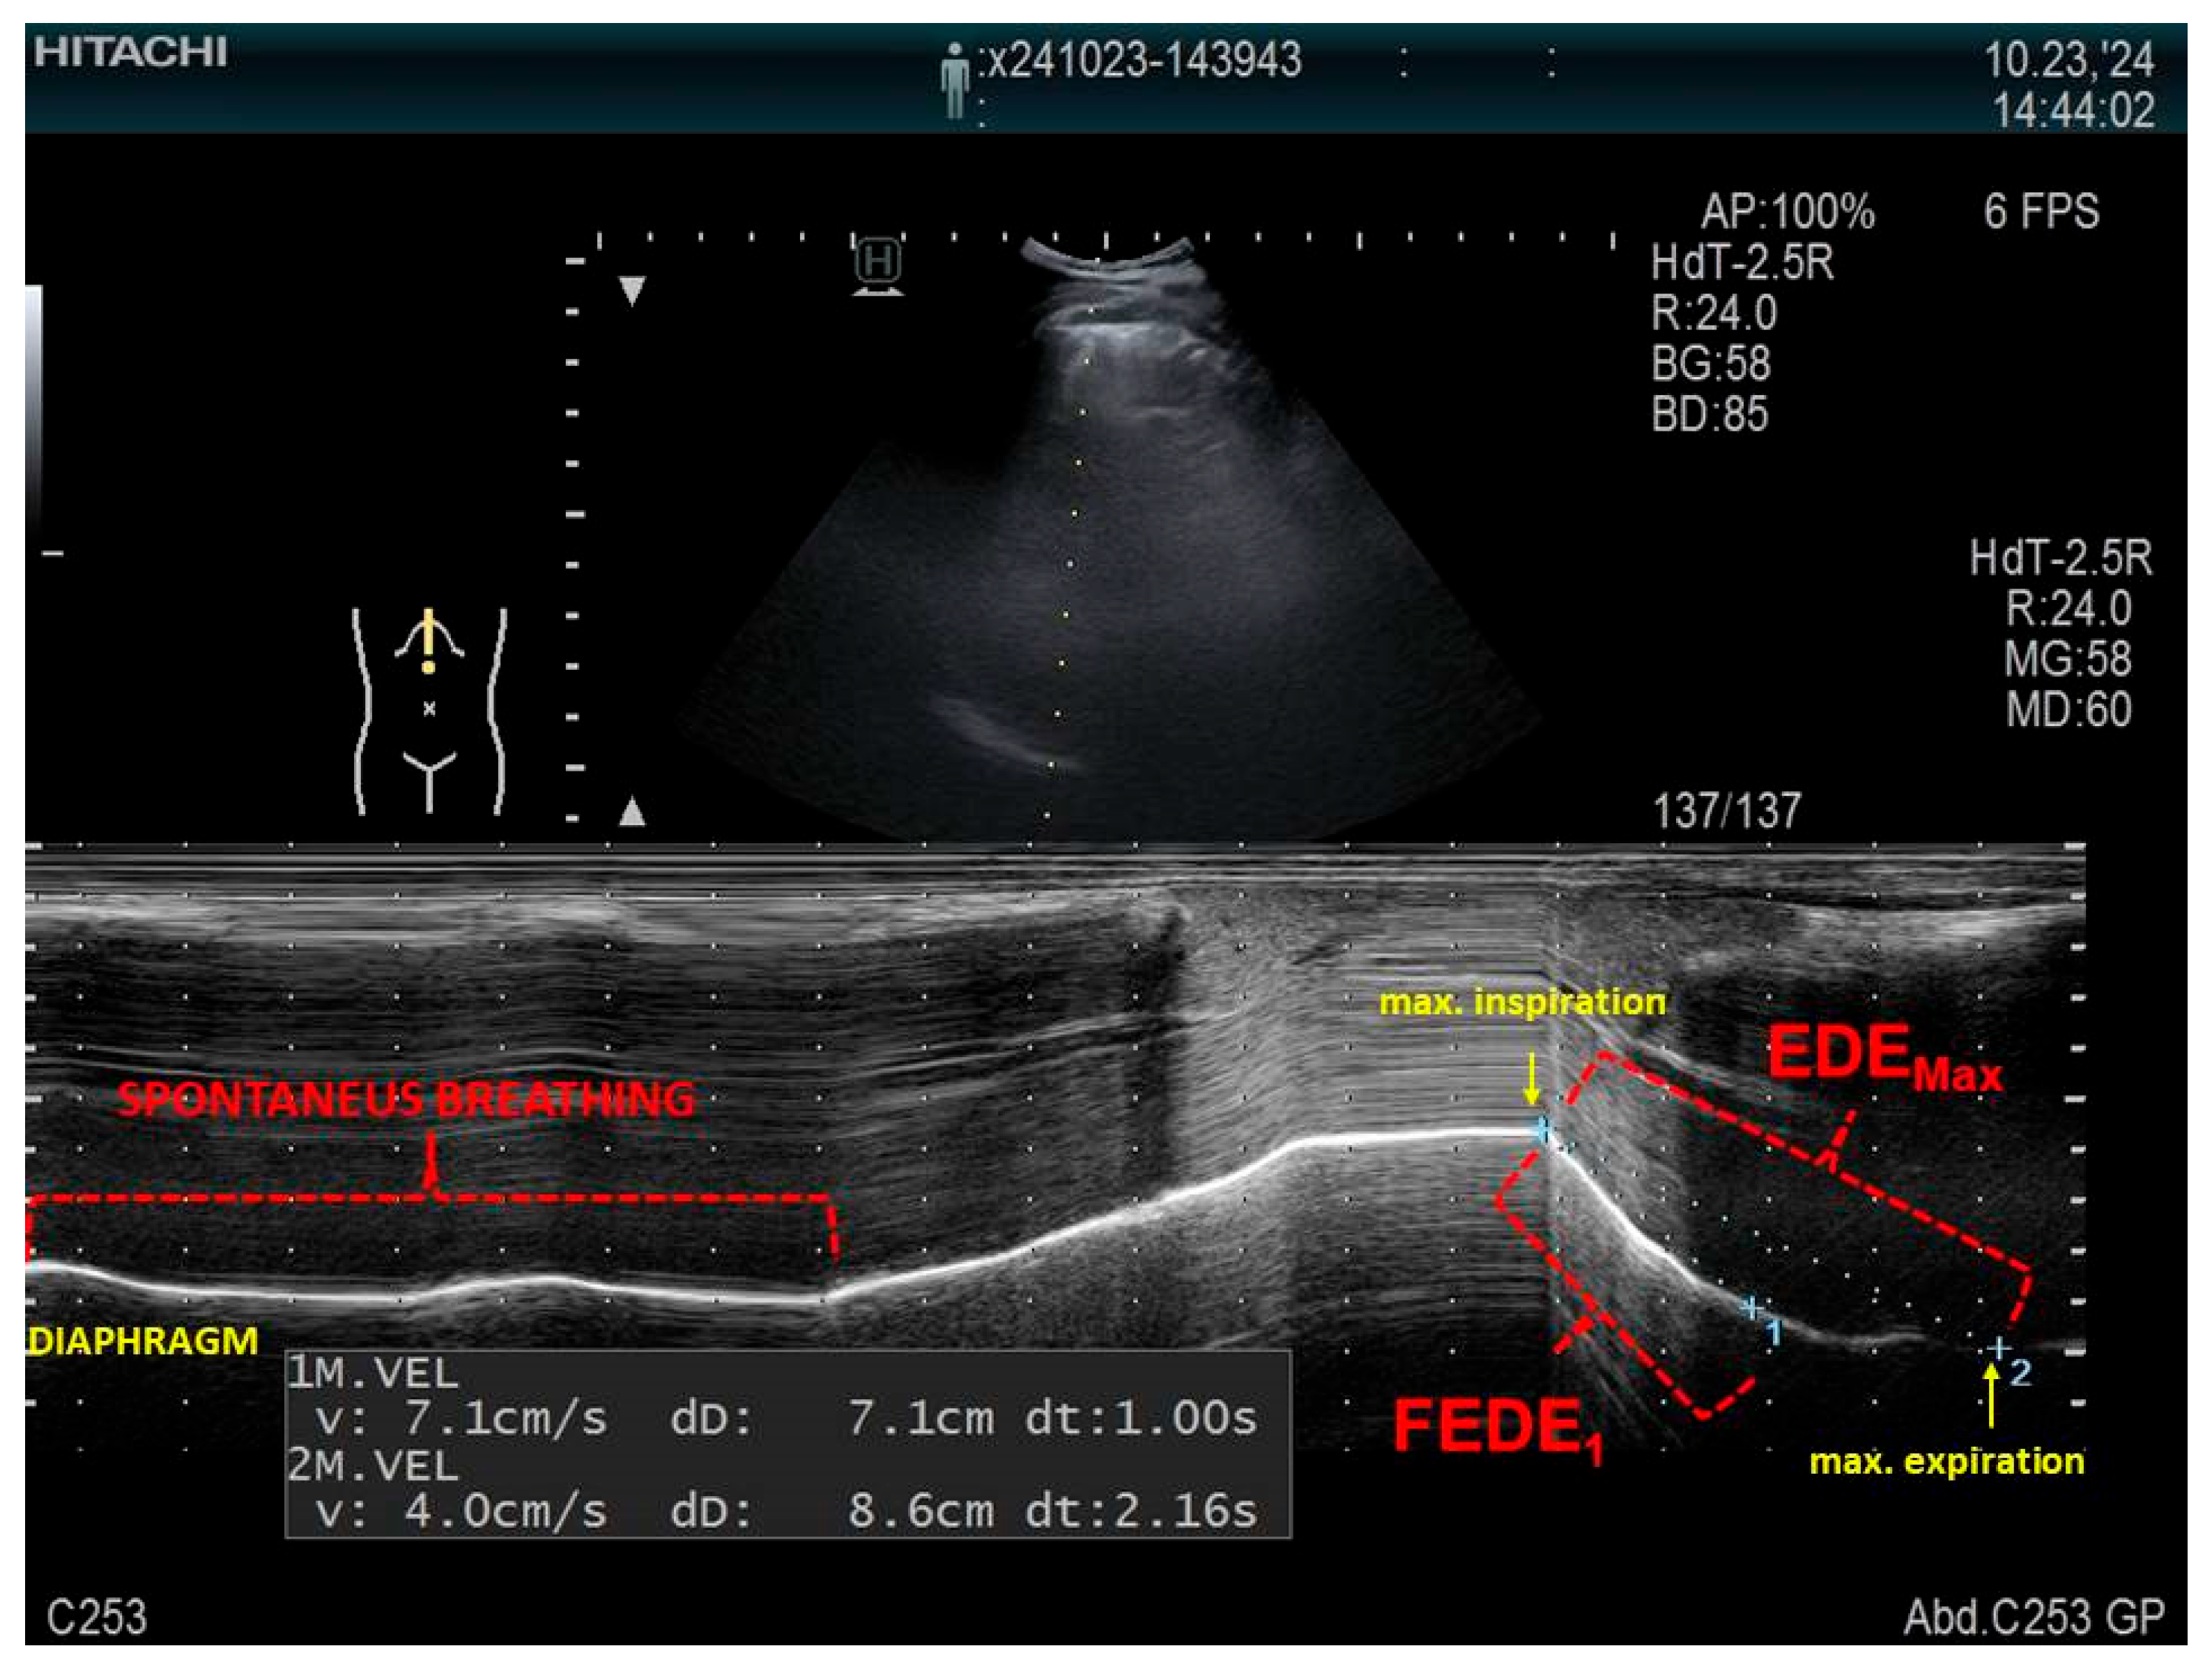

- Zanforlin, A.; Smargiassi, A.; Inchingolo, R. Ultrasound analysis of diaphragm kinetics and the diagnosis of airway obstruction: The role of the M-mode index of obstruction. Ultrasound Med. Biol. 2014, 40, 1065–1071. [Google Scholar] [CrossRef]